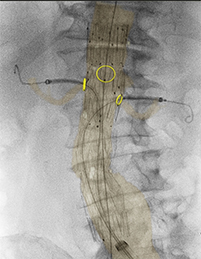

腹部大動脈瘤治療臨床症例1*2 |

*2 出典:Prof. Dr. M. Schermerhorn, BIDMC, Boston, USA, Fenestrated Endovascular Aortic Aneurysm Repair